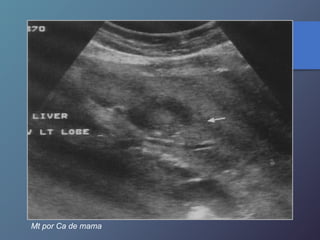

Mt por Ca de mama

Mt por Cade mama